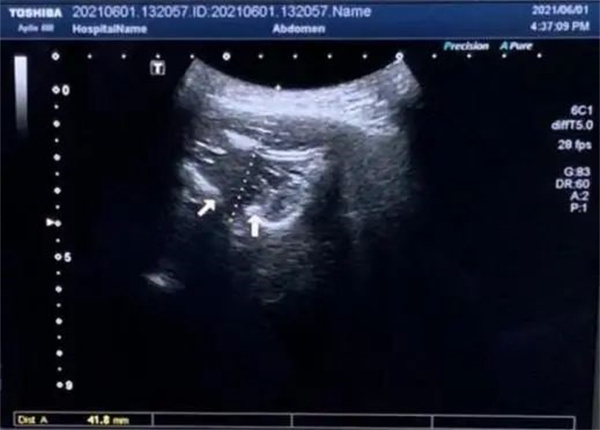

圖4.超聲輔助下進(jìn)針路徑,箭頭示翼腭窩外口骨性標(biāo)志;虛線(xiàn)示:皮膚到翼腭窩外口路徑